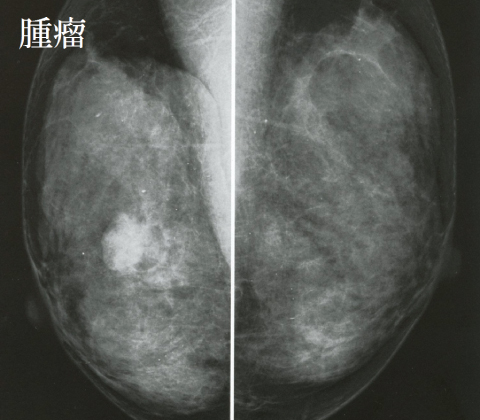

乳房画像

腫瘤

石灰化